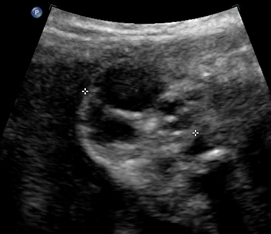

Above. Case 2. 32 1/7 weeks gestation. Sacrococcygeal teratoma. Coronal view of pelvic area. External mass in low sacral area with both cystic and solid components, and little blood flow. The mass appeared completely external to the fetal abdomen.

Case 2. 32 1/7 weeks gestation. Sacrococcygeal teratoma. Some transverse views through the predominant cyst demonstrate no solid areas.

Above. Case 2. 32 1/7 weeks gestation. Sacrococcygeal teratoma. Some views demonstrate both solid and cystic components. There was no evidence for fetal hydrops or polyhydramnios. Delivery occurred following premature labor at 34 1/7 weeks. Skin completely covered the defect and an uneventful repair occurred.